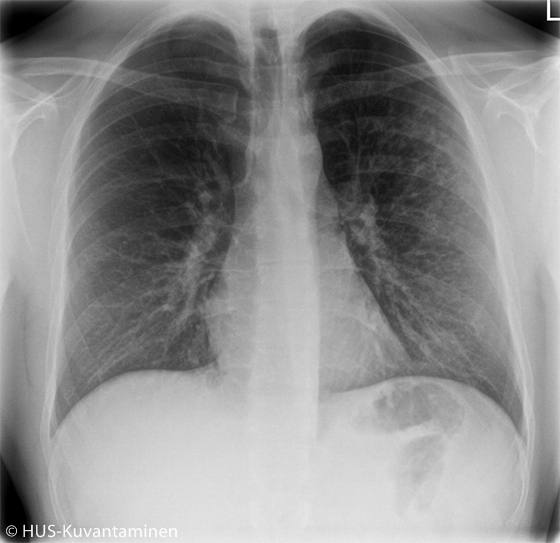

Atypical pneumonia in a patient with HIV (radiograph without markers).

A young man had been coughing and experiencing low-grade fever for 2 weeks. The patient had HIV, which had been managed appropriately. Obstruction was heard in pulmonary auscultation.

The chest X-ray showed atypical pneumonia. There is diffuse shadowing and increased markings in the distal lung parenchyma (circle).